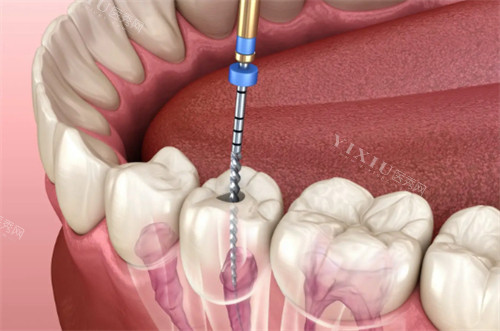

给我看牙的是李医生,他特别有耐心。先是详细地询问了我的症状和病史,然后带我去拍了牙片。拿到牙片后,他一边指着片子,一边给我讲解牙齿的问题,什么龋齿、牙髓炎,说得明明白白,我这个对口腔知识一窍不通的人都能听懂。他还跟我分析了几种治疗方案的优缺点,让我自己选择。这种充分尊重患者意见的做法,让我觉得特别贴心。

确定好治疗方案后,就开始治疗了。说实话,我心里还是挺害怕的,毕竟之前听别人说看牙很疼。李医生好像看出了我的紧张,不断地安慰我,让我放松。在治疗过程中,他的手法特别轻柔,我本来以为会很疼,结果并没有想象中那么难受。而且,医院的设备都很较高,治疗起来又快又有效。